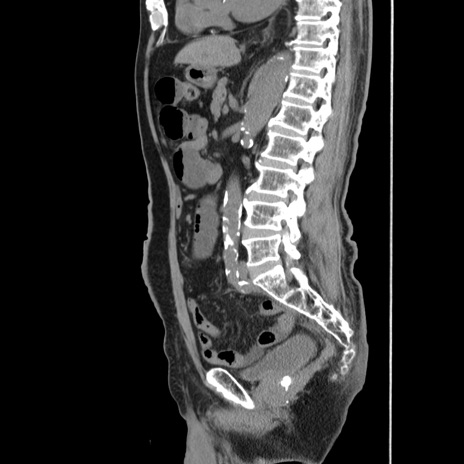

症例24(矢状断像)

【症例】80歳代男性

【主訴】左側腹部痛、嘔吐

【現病歴】本日早朝より左腹部に痛みあり。昼頃嘔吐認めたため、救急要請。

【既往歴】直腸癌(Mile手術)、胆摘

【身体所見】意識清明、BT 35.9℃、BP 221/93mmHg、SpO2 97%(RA) 、腹部:左ストーマ周囲に限局性の腹部膨隆あり。 膨隆部自発痛・圧痛あり・軟。

【データ】WBC 7700、CRP 0.09